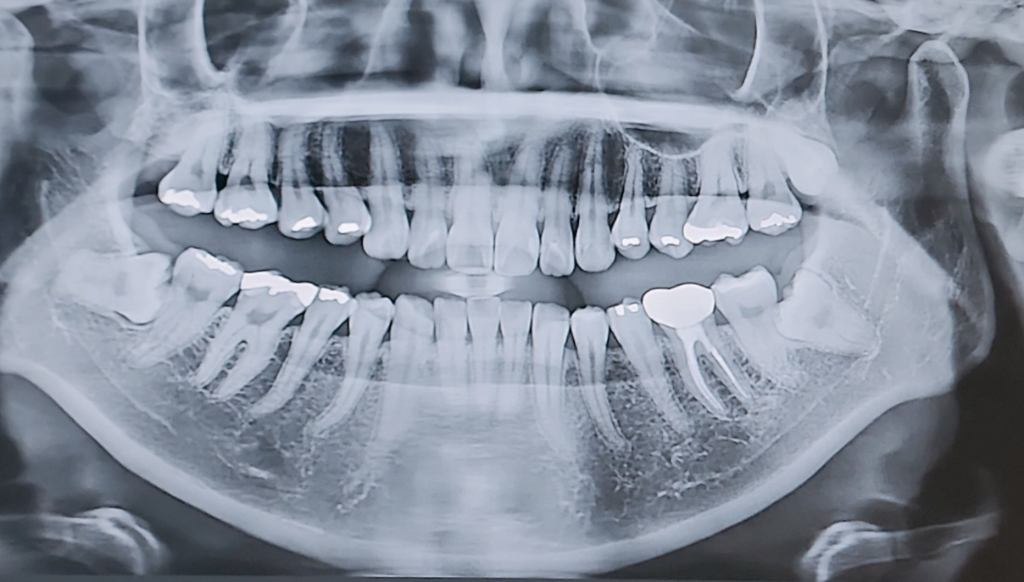

매복사랑니 양쪽다뽑앗는데 양쪽다 질문이있어요

교정및 수술의염두로 인해 매복사랑니를 전부제거예정입니다.

사진 첨부합니다 실밥을 엄청 꼬매주셔서 두쪽 다 드라이소켓같은건 전혀 발생한거같진않아요. 왼쪽 붓기도 아주천천히 빠지고있으나 어금니가아프고 찝힘등으로 잠들기어렵고 밥을못먹는데 어금니통증도 다 자연스러운걸까요? 제 치아상태를보면 그럴수있는건지 궁금합니다.